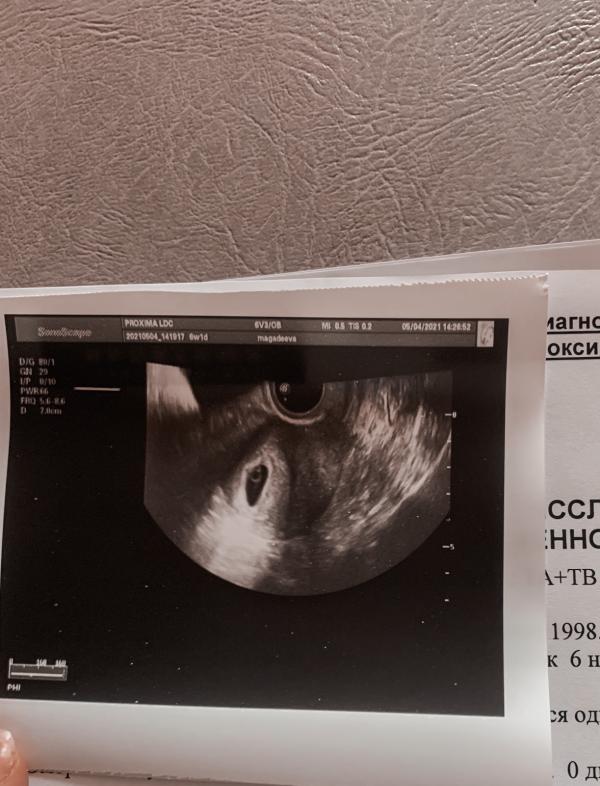

04.05.2021 я ходила на узи для подтверждения беременности.

Беременность подтвердилась, срок по узи 5 недель и 4 дня. 🤰🏼